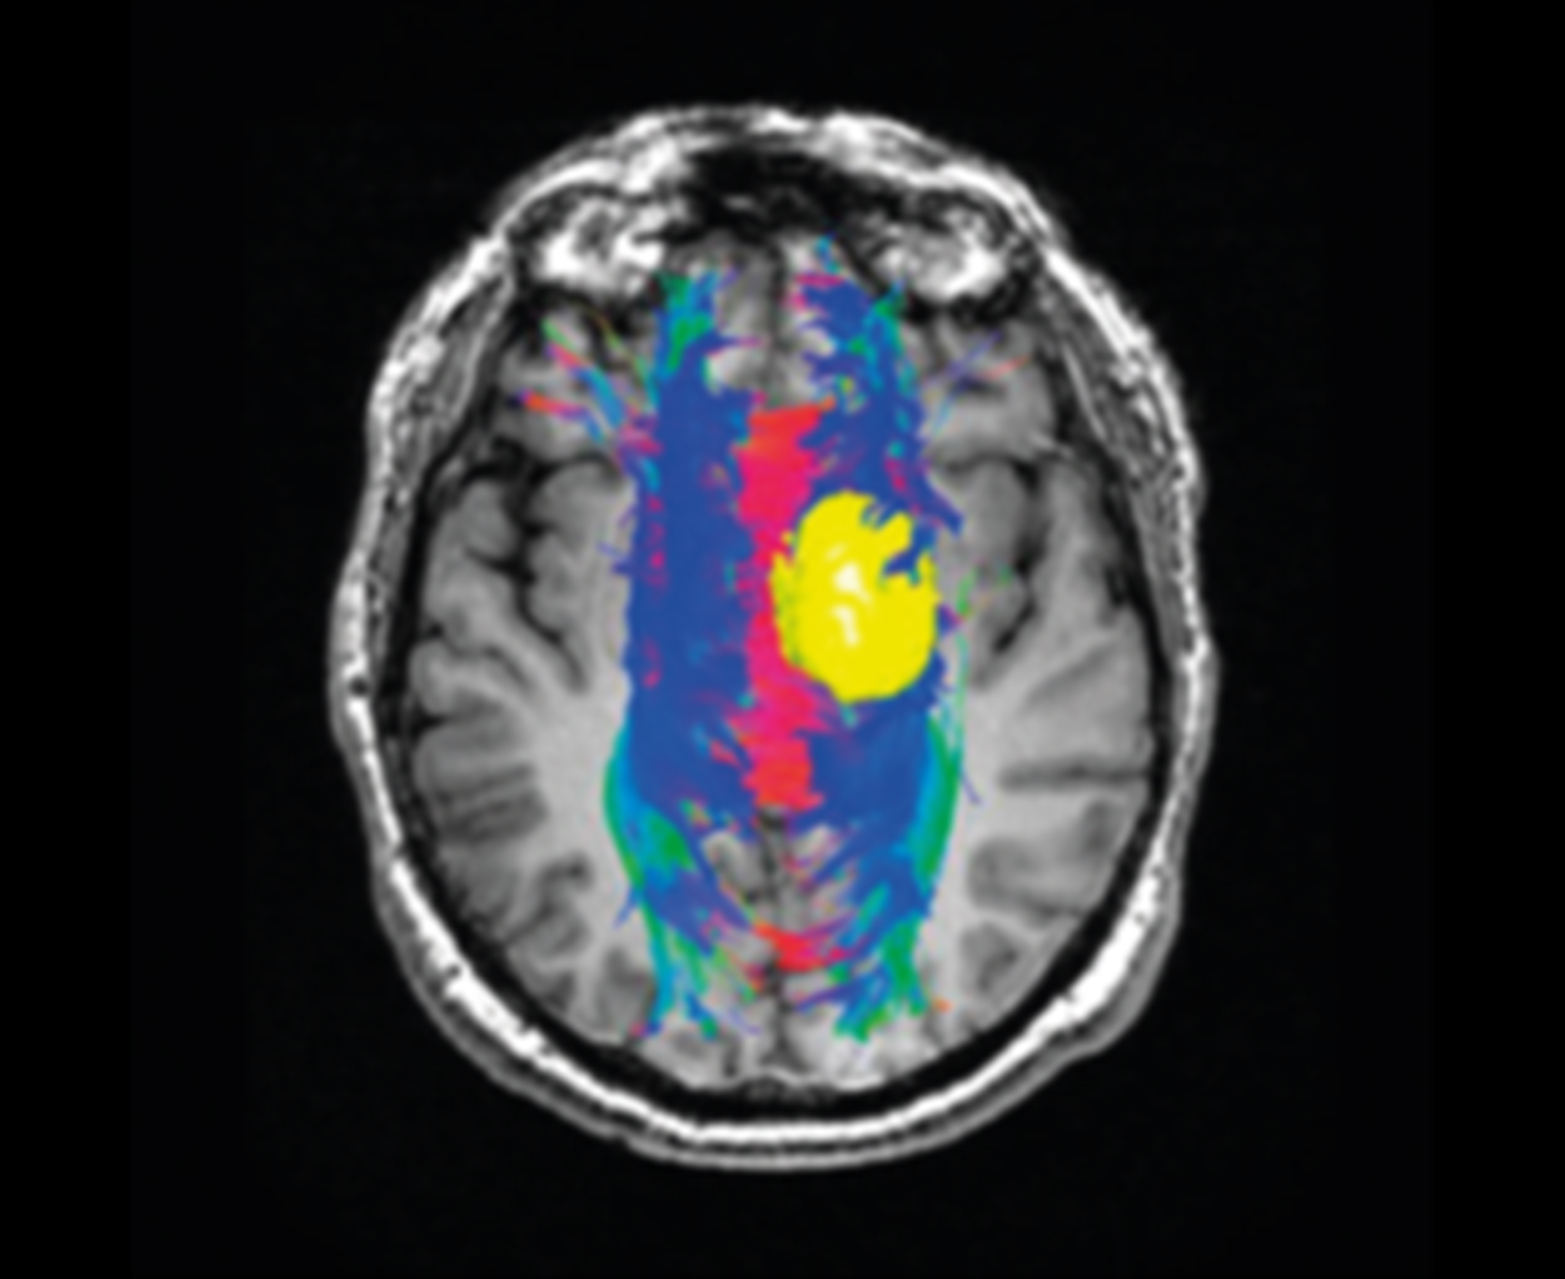

Отслеживание волокна и объединение с обычными картами